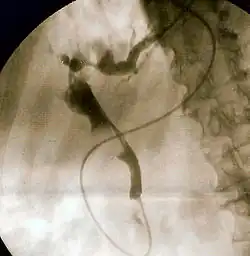

Endoscopic retrograde cholangiopancreatography (ERCP) is a technique that combines the use of endoscopy and fluoroscopy to diagnose and treat certain problems of the biliary or pancreatic ductal systems. It is primarily performed by highly skilled and specialty trained gastroenterologists. Through the endoscope, the physician can see the inside of the stomach and duodenum, and inject a contrast medium into the ducts in the biliary tree and/or pancreas so they can be seen on radiographs.

The patient is sedated or anaesthetized. Then a flexible camera (endoscope) is inserted through the mouth, down the esophagus, into the stomach, through the pylorus into the duodenum where the ampulla of Vater (the union of the common bile duct and pancreatic duct) exists. The sphincter of Oddi is a muscular valve that controls the opening to the ampulla. The region can be directly visualized with the endoscopic camera while various procedures are performed. A plastic catheter or cannula is inserted through the ampulla, and radiocontrast is injected into the bile ducts and/or pancreatic duct. Fluoroscopy is used to look for blockages, or other lesions such as stones.[8][9]

When needed, the sphincters of the ampulla and bile ducts can be enlarged by a cut (sphincterotomy) with an electrified wire called a sphincterotome for access into either so that gallstones may be removed or other therapy performed.[10]

Other procedures associated with ERCP include the trawling of the common bile duct with a basket or balloon to remove gallstones and the insertion of a plastic stent to assist the drainage of bile.[11] Also, the pancreatic duct can be cannulated and stents be inserted.